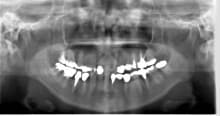

こんにちは。 歯科衛生士の山崎です。 歯周病の治療とその後インプラント治療を行ったケースをご紹介します。 50代 男性の方で、主訴は左下ブリッジに違和感があるとのことでした。 …